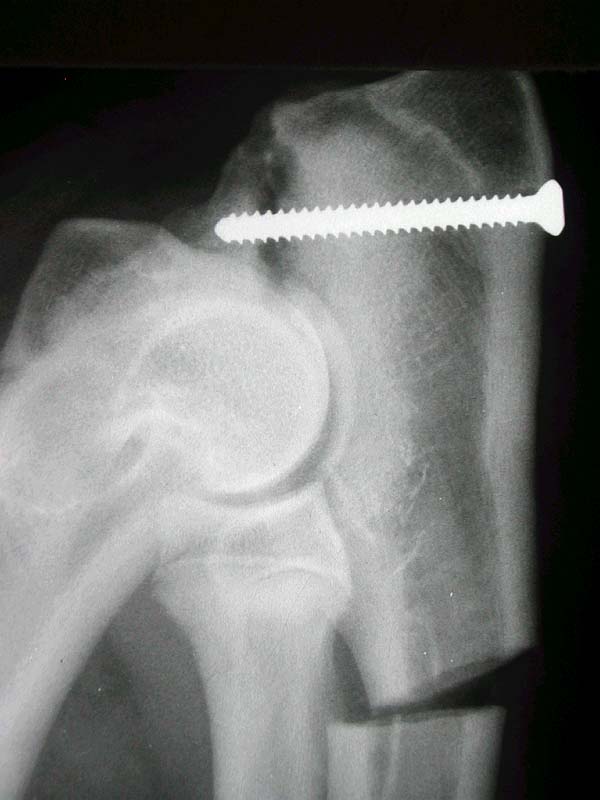

Fractures of the humeral condyle

Fractures of the humeral condyle are the most common fractures to occur in dogs. Because HIF can cause a weakness in the humeral condyle, these fractures can occur during normal activity. Because of the prevalence of HIF in the breed, English Springer Spaniels are prone to condylar fractures but other breeds such as French Bulldogs, Yorkshire Terriers and Labrador Rertrievers are also at increased risk

We have a particular interest in condylar fractures at Movement Vets. Ben Walton has worked with Fusion Implants to develop ‘anatomical plates’ which are specifically designed to treat these fractures in Springer Spaniels and French Bulldogs. These plates help the surgeon to accurately reduce the fractures and ensure that screws are in the optimal location. You can read more about our work on condylar fractures here.